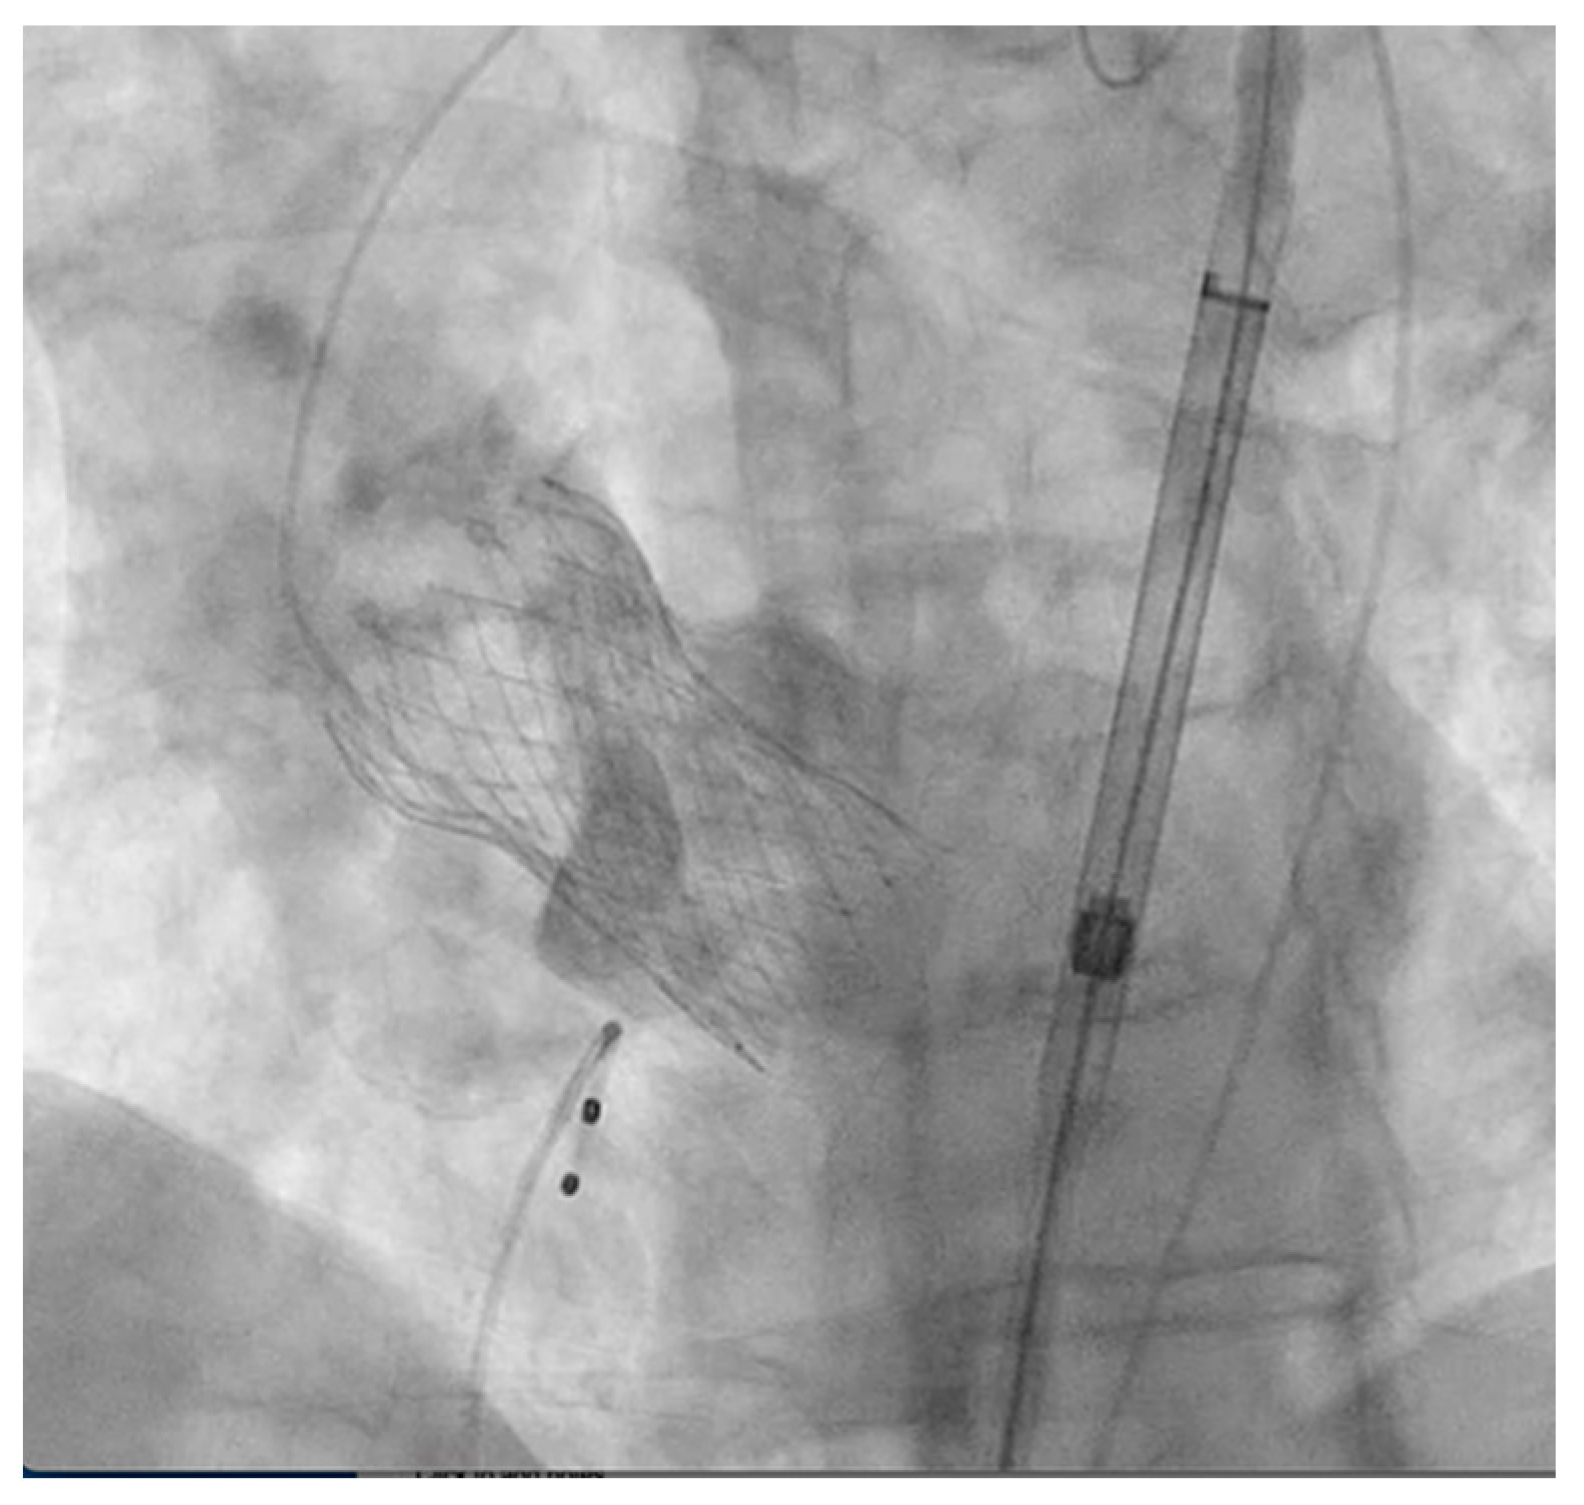

2. Detailed Case Description